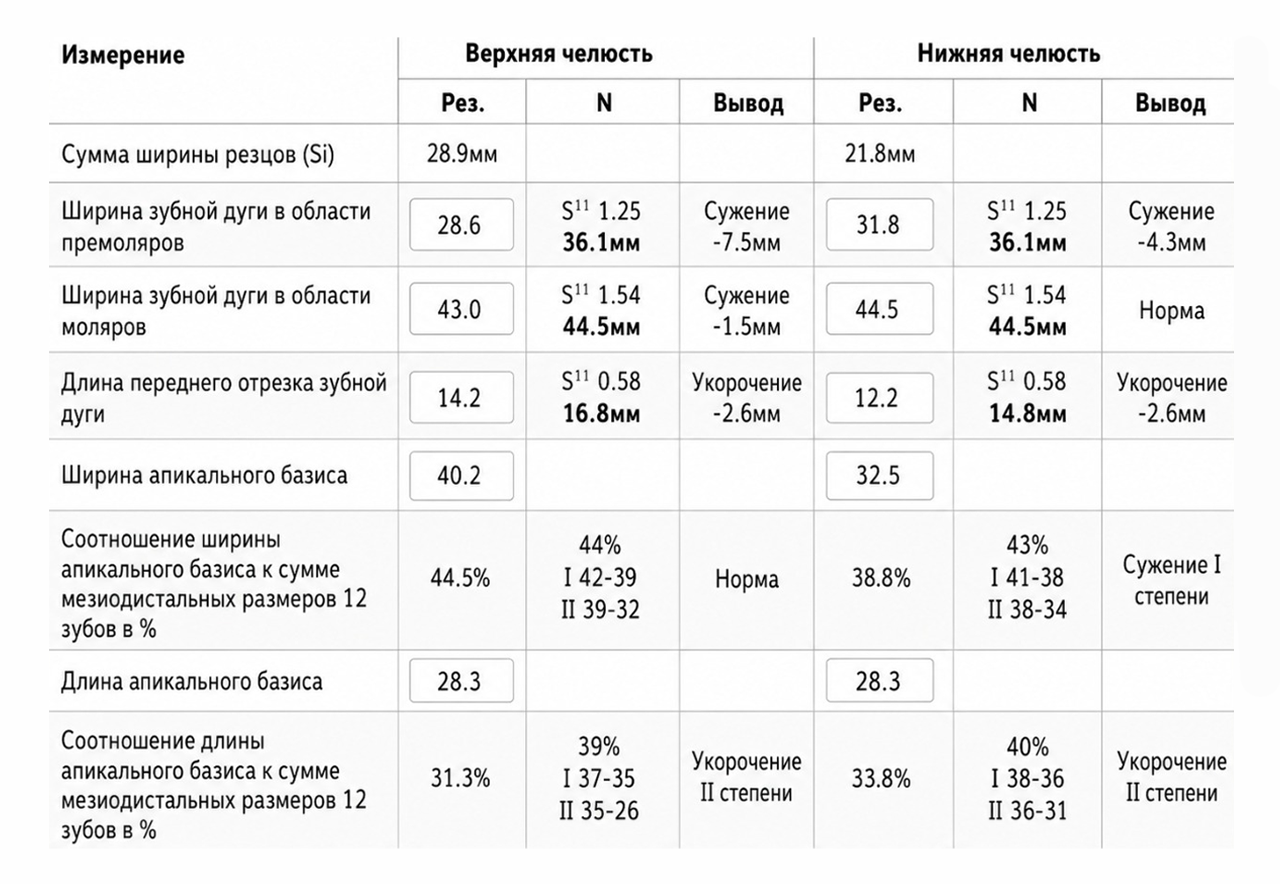

- С помощью специального программного обеспечения с математической точностью производим все рассчеты будущего лечения.

Будут произведены математические рассчеты будущего лечения